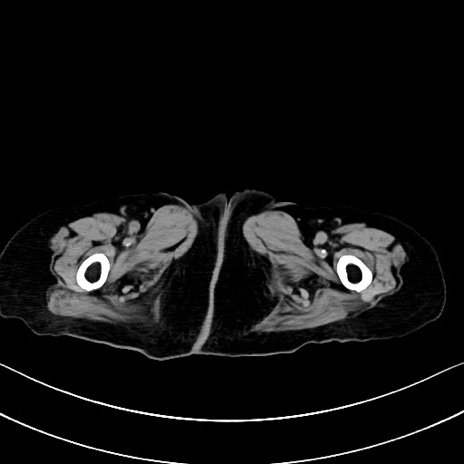

症例40(横断像)他院1日前

横断像